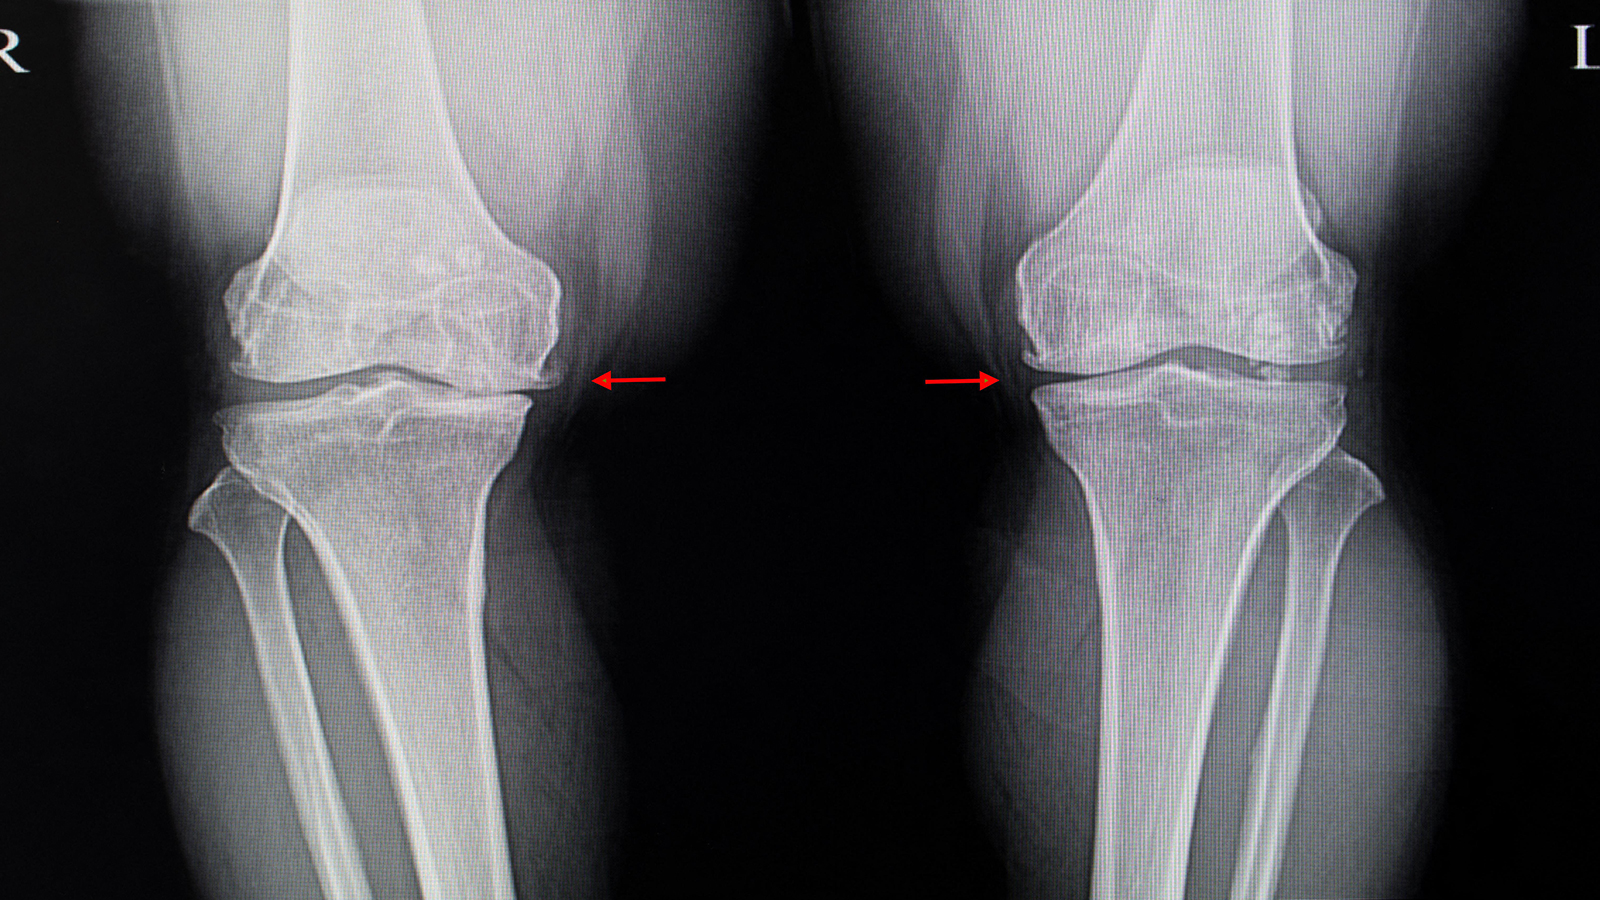

(MedPage Today) — Hopes that the plant extract known as diacerein could relieve pain and disability from osteoarthritis (OA) of the knee now seem forlorn in the wake of an Australian trial that failed to find any benefit.

Among 262 patients with…